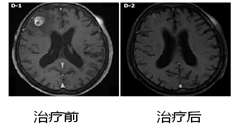

立体定向放射外科的发明人是神经外科医生,同样,颅内肿瘤也是立体定向放疗的主要适应症。而射波刀是颅内肿瘤最佳立体定向放疗手段,也是当前颅内肿瘤的的顶级治疗手段之一。因为射波刀颅骨追踪的优势,使射波刀治疗极为精准。同时,射波刀治疗颅内原发肿瘤和转移瘤不像其他立体定向放疗需要颅骨打孔等,射波刀治疗准备没有创伤。再有,射波刀可以分多次治疗,减轻了治疗副反应。射波刀对于颅内肿瘤的控制率在97%以上。对于颅底,脑干等手术切除难度较大或者手术禁区,射波刀可以大施拳脚,发挥优势,有效控制肿瘤,挽救患者生命。对对于海绵窦血管瘤等无法手术颅内病灶,射波刀更是当前主流治疗手段。对于垂体瘤,颅内动静脉畸形,三叉神经痛等病变,射波刀也可以发挥优异的疗效。

图3 脑干原发肿瘤射波刀治疗疗效(脑干病灶完全消失)

图4 肺癌脑干转移射波刀治疗疗效(5年内患者病灶完全消失,没有任何反应。引自Zhuang HQ,et al.)

图5脑转移瘤射波刀治疗疗效(治疗后病灶完全消失,引自WJG)

图6 颅内海绵状血管瘤射波刀治疗(治疗后病灶基本消失,患者症状完全缓解,连续复查4.5年没有复发,引自Wang X, et al.)